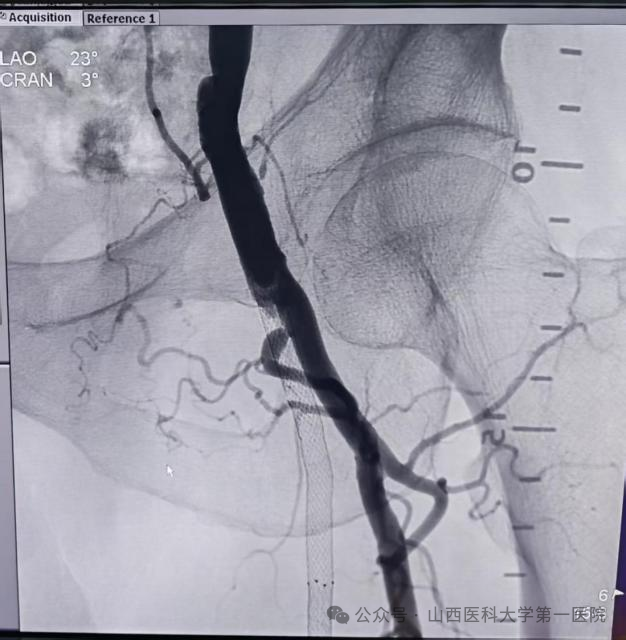

旋切术中动脉造影:左侧股浅动脉显影